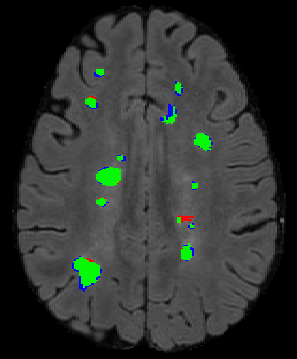

The detection of new multiple sclerosis (MS) lesions is an important marker of the evolution of the disease. The applicability of learning-based methods could automate this task efficiently. However, the lack of annotated longitudinal data with new-appearing lesions is a limiting factor for the training of robust and generalizing models. In this work, we describe a deep-learning-based pipeline addressing the challenging task of detecting and segmenting new MS lesions. First, we propose to use transfer-learning from a model trained on a segmentation task using single time-points. Therefore, we exploit knowledge from an easier task and for which more annotated datasets are available. Second, we propose a data synthesis strategy to generate realistic longitudinal time-points with new lesions using single time-point scans. In this way, we pretrain our detection model on large synthetic annotated datasets. Finally, we use a data-augmentation technique designed to simulate data diversity in MRI. By doing that, we increase the size of the available small annotated longitudinal datasets. Our ablation study showed that each contribution lead to an enhancement of the segmentation accuracy. Using the proposed pipeline, we obtained the best score for the segmentation and the detection of new MS lesions in the MSSEG2 MICCAI challenge.